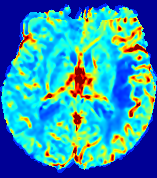

Slice #1Slice #2Slice #3Slice #4Slice #5Slice #6Dgtsuperscript𝐷gtD^{\text{gt}}Refer to captionRefer to captionRefer to captionRefer to captionRefer to captionRefer to caption(a)Refer to captionRefer to captionRefer to captionRefer to captionRefer to captionRefer to caption(b)Refer to captionRefer to captionRefer to captionRefer to captionRefer to captionRefer to caption(c)Refer to captionRefer to captionRefer to captionRefer to captionRefer to captionRefer to caption(d)Refer to captionRefer to captionRefer to captionRefer to captionRefer to captionRefer to caption(e)Refer to captionRefer to captionRefer to captionRefer to captionRefer to captionRefer to caption(f)Refer to captionRefer to captionRefer to captionRefer to captionRefer to captionRefer to captionRefer to caption000.060.060.060.120.120.120.180.180.180.240.240.240.300.300.30(mm2/s)𝑚superscript𝑚2𝑠(mm^{2}/s)

Figure 13: PIANO effectiveness and robustness testing: diffusion imaging via diffusion. Top row shows Dgtsuperscript𝐷gtD^{\text{gt}} used for simulating the ground truth pure diffusion. (a)-(f) refer to the results for D𝐷D estimated from the ground truth pure diffusion image time-series where Rician noise at levels 0%, 2%, 4%, 6%, 8%, 10% was added respectively.

Similarly, starting from the same initial condition C0superscript𝐶0C^{0} as in the ‘Advection Imaging’ experiment for each patient, we simulate concentration time-series {Cti(Ω)|i=0, 1,, 40}conditional-setsuperscript𝐶subscript𝑡𝑖Ω𝑖0140\{C^{t_{i}}\in\mathbb{R}(\Omega)|i=0,\,1,\,\ldots,\,40\} via a diffusion PDE, where we define the ground truth diffusivity D:=Dgtassign𝐷superscript𝐷gtD:=D^{\text{gt}} via the ADC map of the ISLES 2017 training set (ADC values are scaled by 0.000010.000010.00001 to ensure numerical stability):

C(𝐱,t)t=(D(𝐱)C(𝐱,t)).𝐶𝐱𝑡𝑡𝐷𝐱𝐶𝐱𝑡\frac{\partial C({\bf{x}},t)}{\partial t}=\nabla\cdot\left(D({\bf{x}})\,\nabla C({\bf{x}},t)\right). (16)

Note this is likely not a spatially representative ground-truth for perfusion imaging, as it measures different effects from diffusion imaging. However, we still use it as a quasi-realistic pattern of diffusivity in the brain. We also added 2%, 4%, 6%, 8%, 10% levels of Rician noise to obtain simulations of ‘Diffusion Imaging’. The estimated Destsuperscript𝐷estD^{\text{est}} given concentrations of all noise levels for one patient are shown in Fig. 13, PIANO estimation results for all patients are summarized in Fig. 11 (b). Again, PIANO demonstrates its capability to recover the underlying diffusion field. In Fig. 13, when the noise level is increasing, some noisy patterns indeed appear in the associated Destsuperscript𝐷estD^{\text{est}}. Note that the ground truth diffusivity applied in this simulation experiment is about ten times larger than the diffusivity estimated in reality (Fig. 3, Fig. 4).